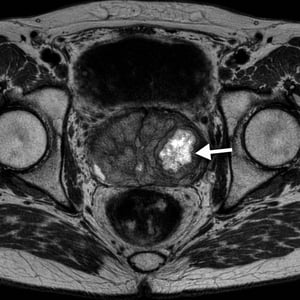

MRI Visibility

MRI visible tumors allow for greatest treatment precision. TULSA-PROTM relies on real-time MRI guidance for precise targeting and minimal collateral damage.

Large Prostatic Calcifications

Calcifications can affect safety and results. Detailed analysis performed by Dr. Hong before the procedure.